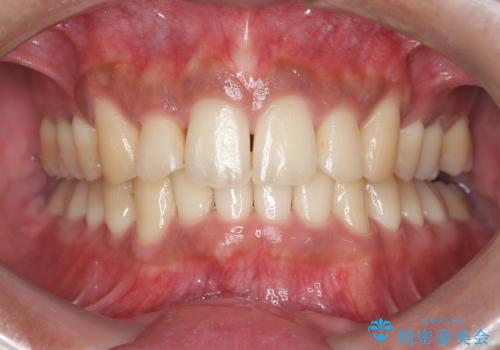

前歯のデコボコと深い咬み合わせを解消

今回の矯正治療では、まず歯が並ぶスペースを確保するため、上顎の小臼歯を抜歯しました。抜歯によってできたスペースを利用して前歯を奥へ移動させ、デコボコを解消。同時に、奥歯の咬み合わせを調整することで、深すぎた咬み合わせであるディープバイトも改善しました。治療の結果、長年気にされていた前歯のデコボコが解消され、理想的な歯並びに。さらに、正しい咬み合わせを獲得したことで、機能的にも安定した美しい口元になりました。